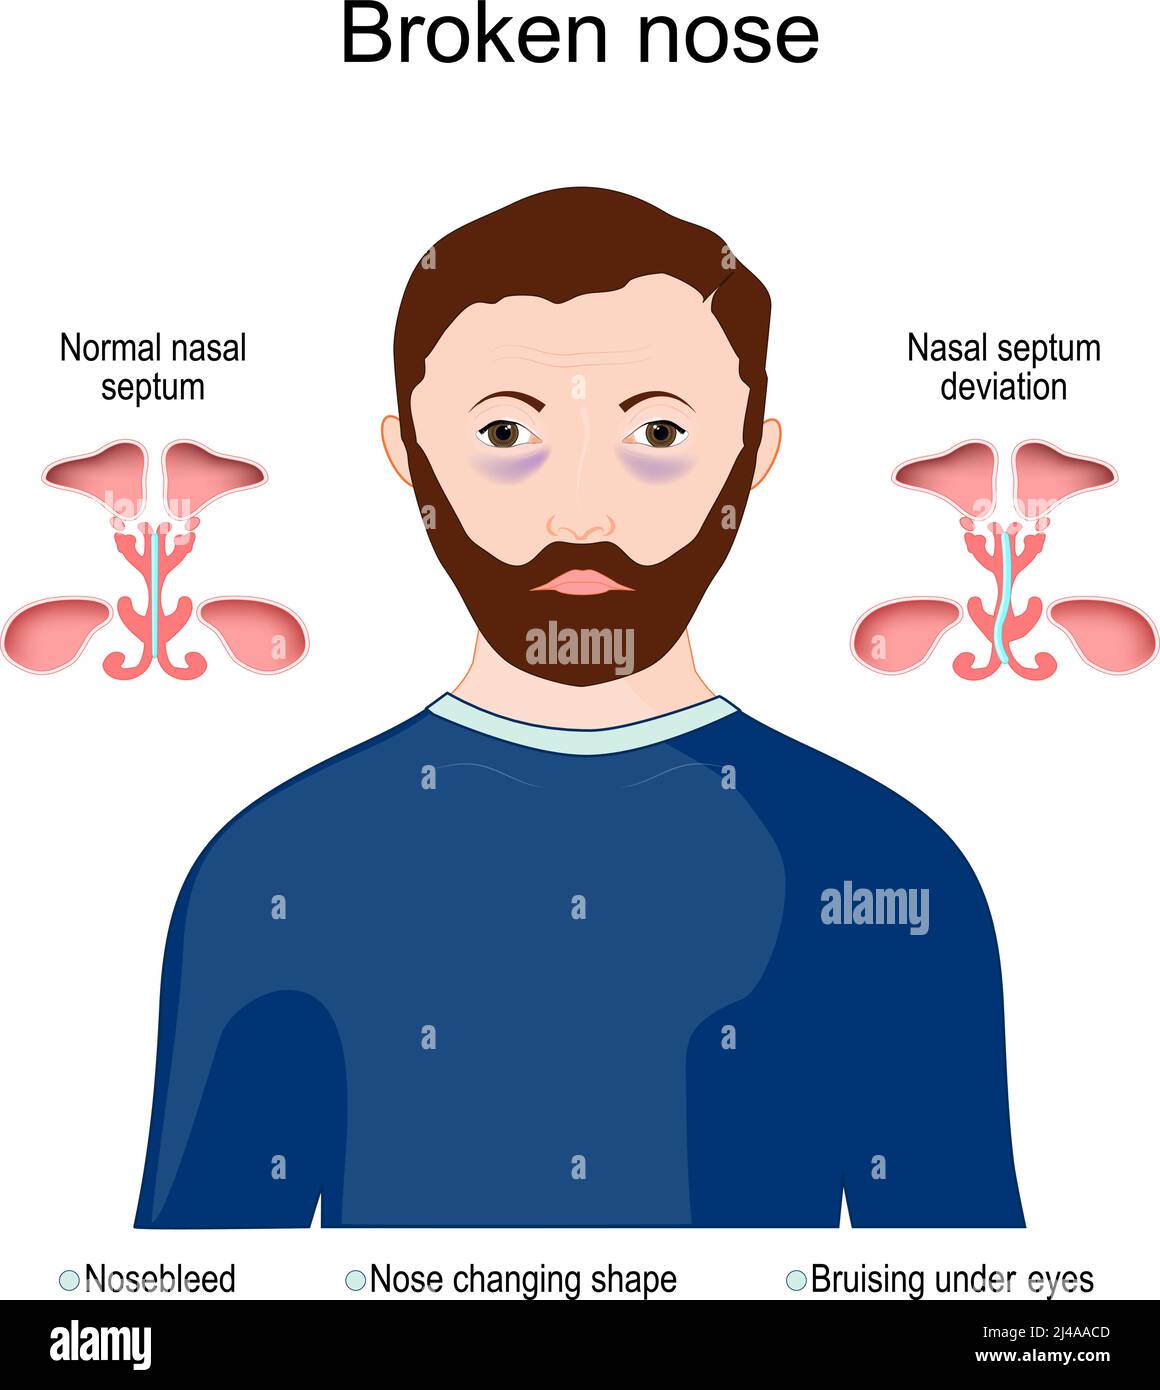

dinosenglish.edu.vnBroken Nose | Nasal Bone Fracture Aetiology And Management

dinosenglish.edu.vnBroken Nose | Nasal Bone Fracture Aetiology And Management

www.med2date.comnose broken nasal fracture bone management common aetiology males incidence due position

www.med2date.comnose broken nasal fracture bone management common aetiology males incidence due position